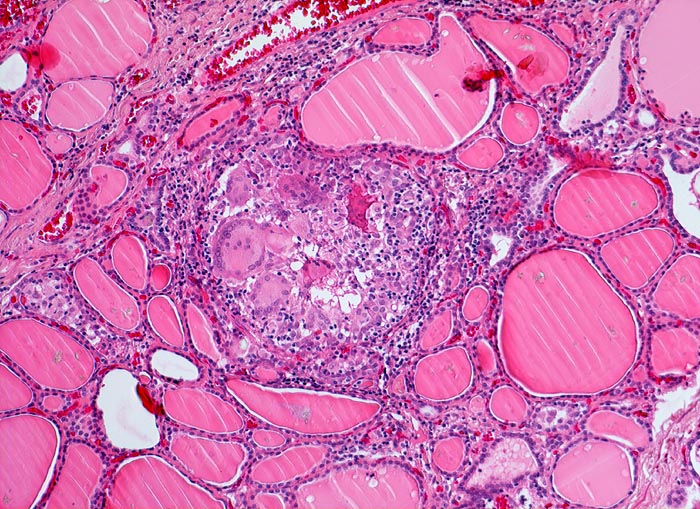

AP/ Subakute Thyeroiditis de Quervain

Subakute Thyeroiditis de Quervain

Schilddrüse

Morphologie